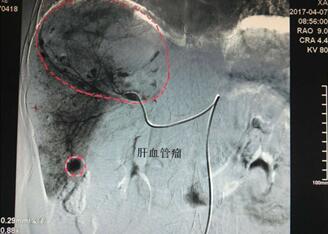

4月7日上午8时30分,介入科顺利完成一例巨大血管瘤介入栓塞治疗。

患者孙某,女性,62岁,在我院体检时发现患有巨大肝血管瘤(130mm×88mm),4月7日,患者在我院介入科施行介入微创手术治疗。术前,科主任李建国详细分析评估了病情,组织科室人员制定了严密的手术方案,术中精细操作,在全体医护人员的密切配合下,历时40分钟,成功对患者肝脏巨大血管瘤实施了肝动脉超选择介入栓塞术。治疗过程患者处于清醒状态,无痛苦,术后生命体征正常,安返病房。

据介绍,肝血管瘤患者通常是在体检时发现,药物治疗几乎无效,传统的方法是外科手术,但因手术风险大,术后恢复时间长,对身体创伤比较大,成为了患有肝血管瘤患者的最大心病。

近年来,肝血管瘤的微创治疗发展非常迅速,符合以下5种情况可以考虑介入治疗:肝血管瘤大于5厘米,有明显压迫症状或疼痛者;肝血管瘤邻近肝包膜,有破裂风险者;肝血管瘤已经破裂出血者(这个必须做,介入栓塞止血效果非常好);不能开刀切除或不愿接受开刀治疗者;定期复查时发现肝血管瘤短时间迅速增大者。

介入微创治疗肝血管瘤的最大优点有三个:创伤小,小小的穿刺口只要消消毒,然后用一个创口贴贴上就行,不用换药不用消炎药;对肝功能影响小,随着微导管等介入材料的发展,肝功能有时基本上不会受到损害,或只有一点点损伤,几天就恢复了;风险低、住院天数短。随着我院介入科对该类手术的熟练开展,将使渭南及周边区域更多患者受益。